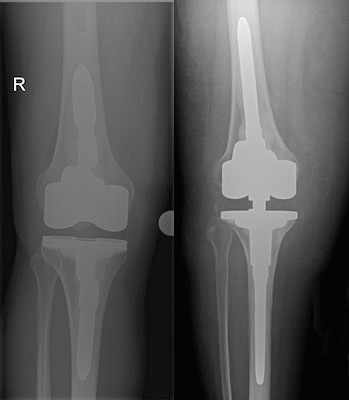

Die Arthrose verläuft also in verschiedenen Stadien, die gut auf dem Röntgenbild sichtbar und zu beurteilen sind, weshalb das Röntgenbild das wichtigste Diagnostikum bezüglich der Arthrose ist.

Das Kniegelenk besteht aus drei Gelenkkompartimenten: einem inneren, zentralen und äußeren Kompartiment. Die Kniescheibe bildet ein Widerlager und gleitet über den Oberschenkelknochen. Prinzipiell ist ein isolierter oder kombinierter Verschleiß vom inneren oder äußeren Gelenkkompartiment sowie auch dem Kniescheibenwiderlager möglich. Erkennt man die Erkrankung früh genug und ist der Leidensdruck entsprechend, so kann man die einzelnen Kompartimente isoliert ersetzen.